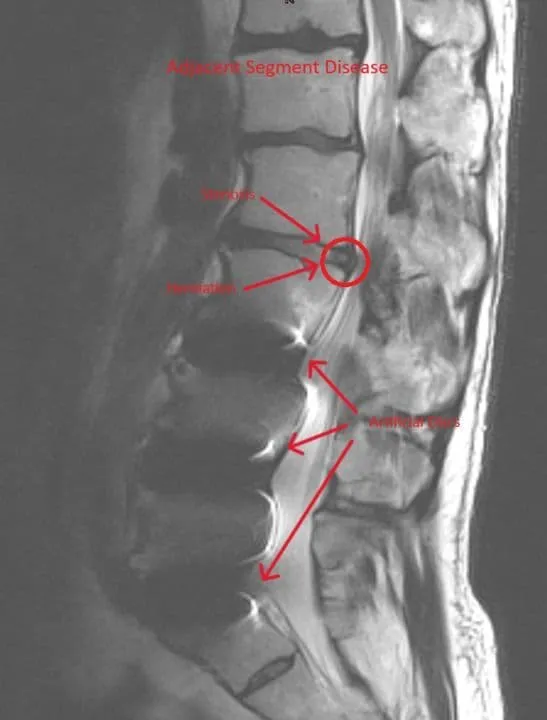

Adjacent Segment Disease

MRI of lumbar spine showing recurrent disc herniation post discectomy highlighted by arrows.

Recurrent Herniation

Recurrent Disc Herniation

20-30% recurrence rate as disc material herniates through the same untreated annular tear, requiring repeat surgery.

Residual Stenosis

Stenosis persists or reoccurs commonly after discectomy, requiring additional decompression surgery.